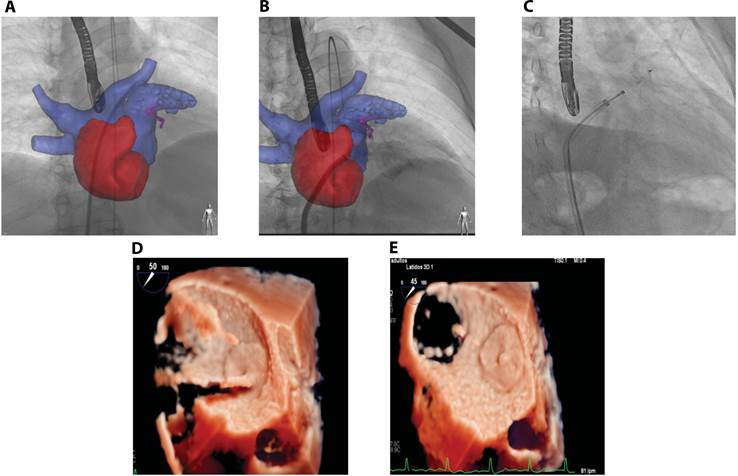

Para el paciente de 62 años se realizó un implante exitoso a primera intención del dispositivo AmuletTM # 28 para cierre de OI, punción trans septal con aguja BRK guiada por ultrasonido que permitió cruce hacia atrio izquierdo, luego se colocó el catéter en la vena pulmonar superior izquierda Figura 2, se intercambió la guía de alto soporte y se procedió a la liberación del dispositivo con catéter Pigtail en la OI B y C, el procedimiento fue bien tolerado, sin complicaciones y verificado por ETE D y E.

Figura 2 TAC con sistema Heart Navigator y acceso a vena pulmonar superior izquierda. A y B. proceso de liberación de dispositivo por cardiólogo intervencionista. D. imagen de ecocardiograma trans esofágico fotograma de adquisición volumétrica 3D modo zoom, con técnica de transiluminación enfocado en orejuela izquierda muestra el proceso de verificación, se observa adecuada posición de dispositivo amplatzer en ese momento no liberado, en la E. se muestra el resultado final del dispositivo liberado.